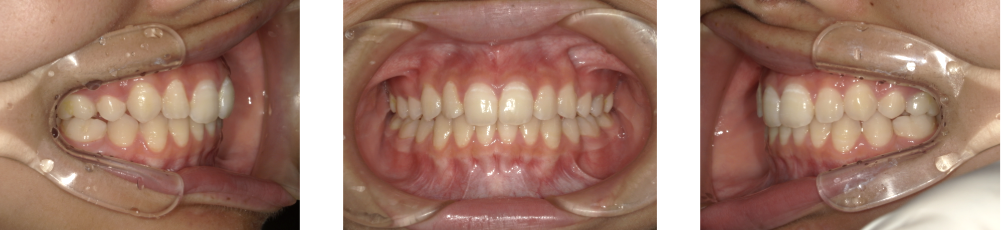

三嶋先生の叢生治療症例

Before Photo

Before

After Photo

After

主訴

ガタガタ、八重歯が気になる。

治療期間

1年11ヶ月

料金

相談料0円、検査料33,000円、動的矯正治療費990,000円、保定装置料5,500円×2枚(必要枚数)

治療概要

上下の個々の歯の大きさに対して、上下の顎が共に小さく、歯が並ぶ余地が不足したために、改善には、上下左右の第一小臼歯を抜歯して空隙を作り、叢生を改善した。